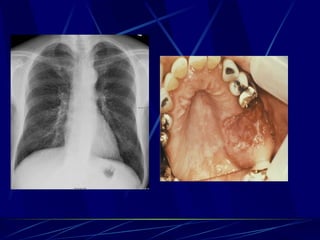

Histoplasma capsulatum Intracelularfacultativo en células RES Causan Neumonía (asintomática usualmente) Hepatoesplenomegalia Lesiones calcificadas Infecciones diseminadas (en SIDA); lesiones mucocutáneas.

Coccidioides immitis EnfermedadValley Fever: neumonia que resuelve, eritema nodoso, artritis Lesiones pulmonares calcifican Sistémica en SIDA: meningitis, lesiones mucocutáneas. Se diseminan en el 3er trimestre del embarazo!

Blastomyces dermatitidis Enfermedad:Blastomicosis: neumonia aguda o crónica Se disemina Ya que no resuelven ocasionalmente, se tratan con ketoconazol